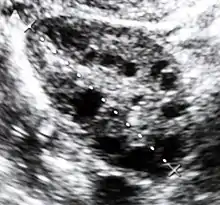

- Les ovaires ont subi des lésions physiques ou contiennent de nombreux kystes affectant leur fonctionnement. Il s’agit de dystrophie ovarienne dans ce cas. Les patientes ayant le syndrome de Stein-Leventhal (ou des ovaires polykystiques, SOPK) souffrent elles aussi d’anovulation[6]. La dysfonction ovulatoire dans le syndrome des OPK est la cause principale des cas d’anovulation[7],[8]. Dans jusqu'à 90 % des cas, l’anovulation est causée par le syndrome des OPK, déséquilibre hormonal généralement héréditaire.